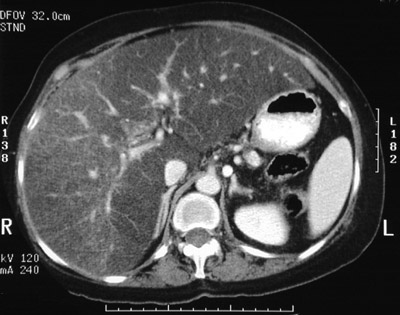

![]() | This abdominal CT scan with contrast reveals a small, shrunken pancreas of decreased density that contains some small calcifications, consistent with chronic pancreatitis. Note the markedly decreased attenuation of the liver, contrasting with the brighter spleen and intrahepatic veins filled with contrast, consistent with severe hepatic steatosis (fatty change). The history of chronic alcoholism for this patient explains both conditions. The right adrenal gland is clearly visible. |